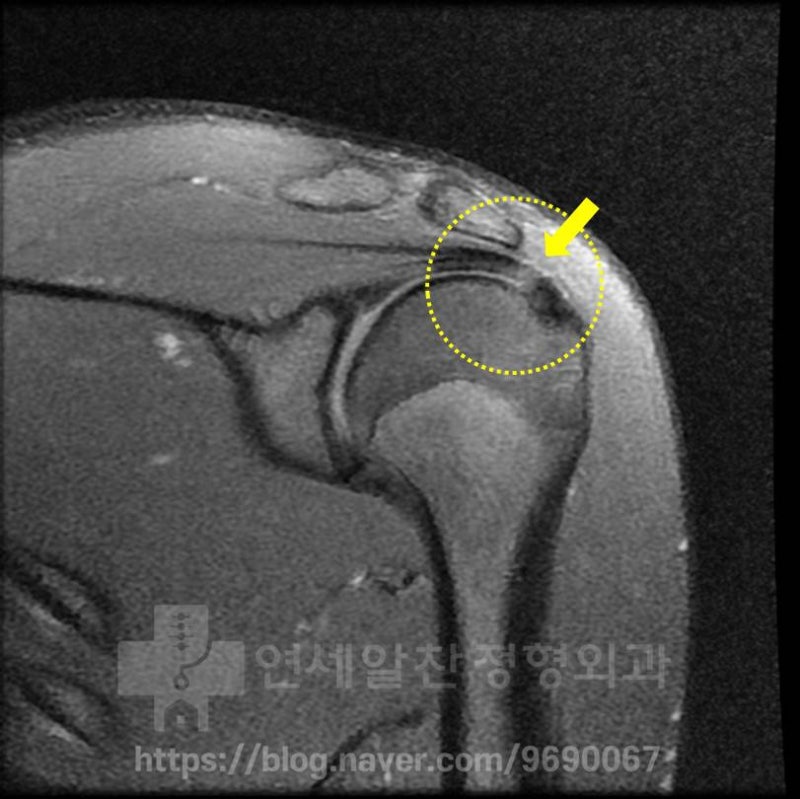

MRI 를 살펴보았을 때 노란 점선안에 보이는 극상근 부위에서 화살표 부위로 표시된 곳이 약간 하얗게 보이는 소견이 관찰됩니다. 이는 극상근내 염증소견이 있는 것을 나타내며 이것을 부분 파열이라고 진단하고 재생주사치료를 한 것으로 보입니다. 하지만 이 MRI 소견으로는 단순 염증 정도로 보이며 파열까지는 진행되지 않은 것으로 보입니다. 시간이 어느정도 경과 되었기 때문에 초음파를 통해 다시 한번 검사를 해 보기로 하였습니다.